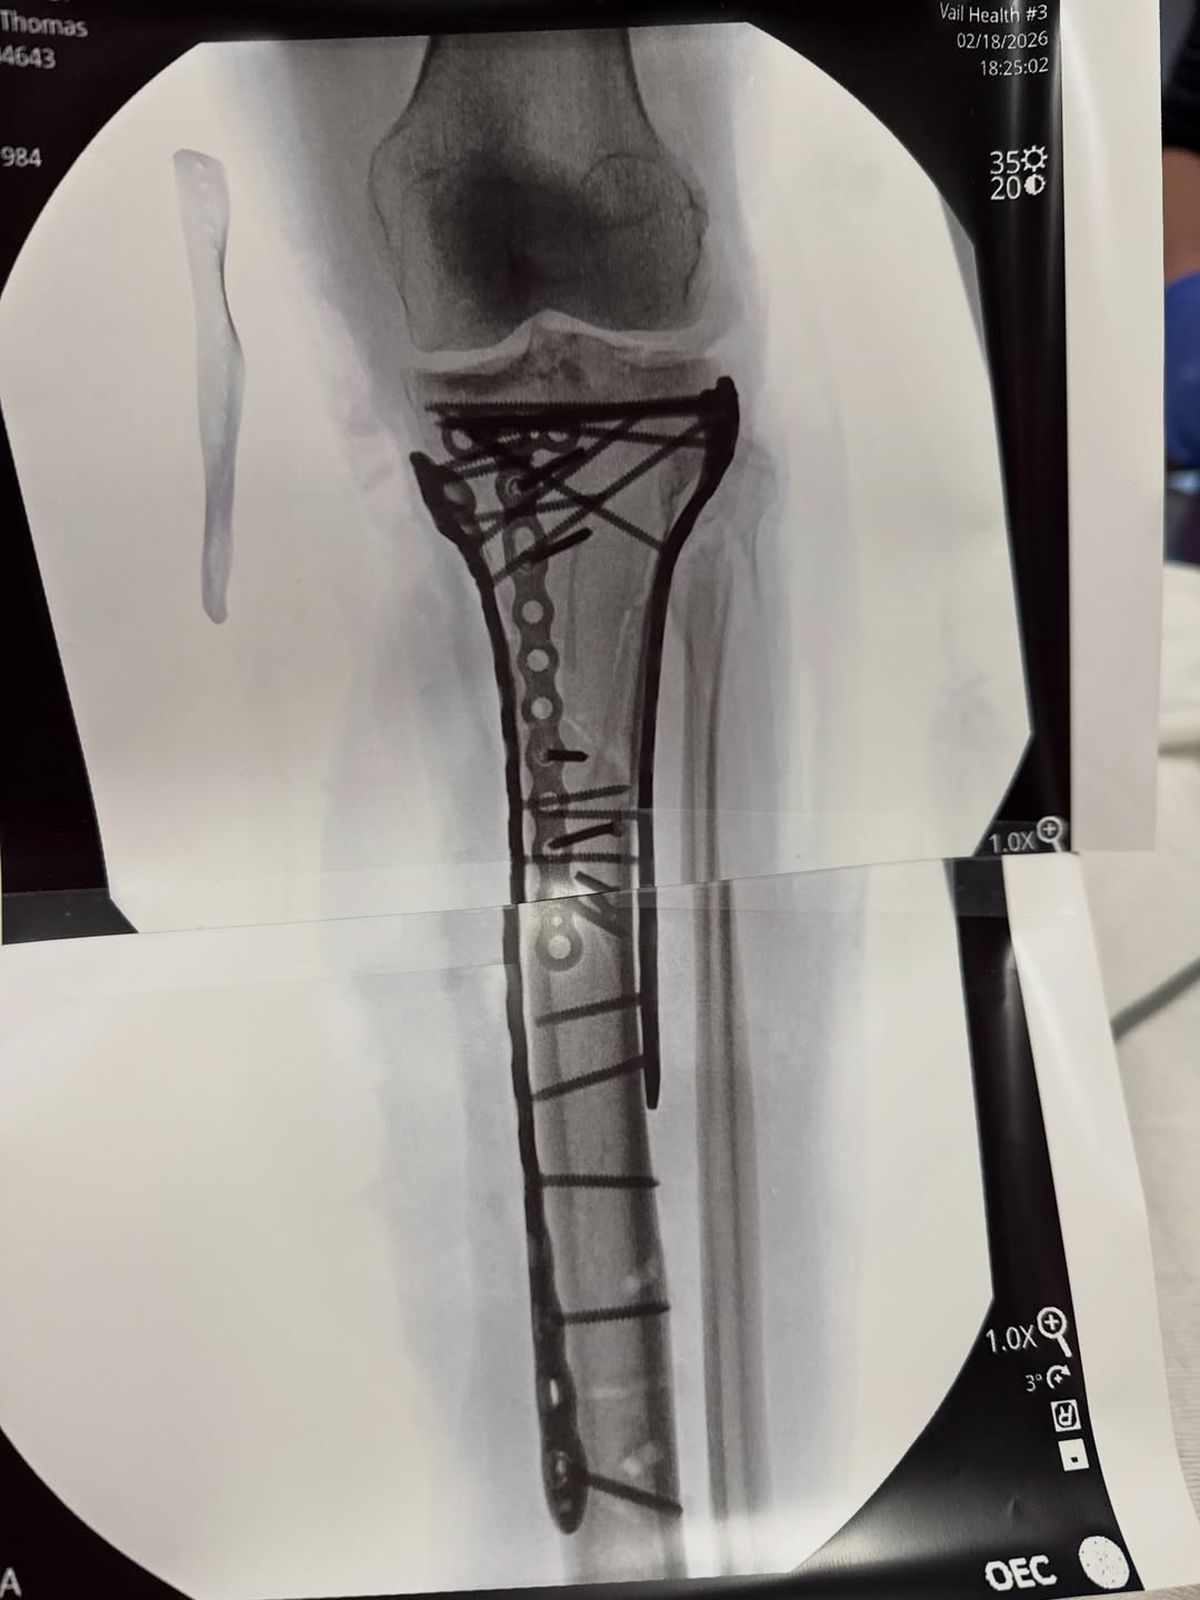

Foto 11/13 : Piciorul lui Lindsey Vonn după operația din 20 februarie // foto: Instagram